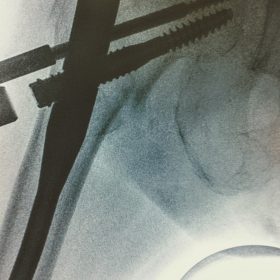

Υποκεφαλικό : Είναι ενδαρθρικό κάταγμα στον αυχένα του μηριαίου (το εσωτερικό του αρθρικού θυλάκου), το οποίο διακόπτει την αιμάτωση της κεφαλής του μηριαίου και οδηγεί σε μη πόρωση του κατάγματος (ΟΣΤΕΟΝΕΚΡΩΣΗ της Μηριαίας κεφαλής). Σε ασθενείς κάτω των 65 ετών αντιμετωπίζεται χειρουργικά με κοχλίωση στις πρώτες 12 ώρες. Τρείς βίδες σε σχήμα Τ με την βοήθεια τηλεόρασης διαδερμικά χωρίς διάνοιξη. Σε ασθενείς από 65-75 ετών γίνεται ολική αρθροπλαστική και σε ασθενείς άνω των 75 ετών αλλάζεται μόνο η κεφαλή χωρίς την αλλαγή της κοτύλης. Ο ασθενής περπατάει άμεσα μετεγχειρητικά στις 5 ώρες και εξέρχεται από το νοσοκομείο σε 1 -2 ημέρες. Στην κοχλίωση μπορεί να εξέλθει και την ίδια ημέρα.